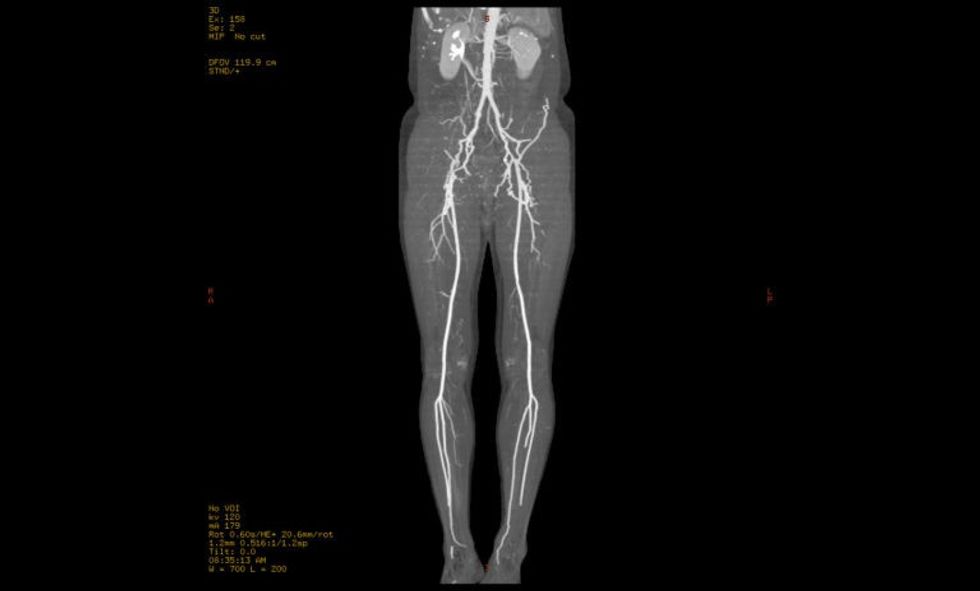

Dr. Idoski: Studimet e fundit tregojnë se goditjet në tru dhe gangrena në këmbë janë më të shpeshta në pranverë. Nëse simptomat dhe ekografia tregojnë rrezik për goditje në tru për shkak të bllokimit të enëve të gjakut që ushqejnë trurin ose gangrenë për shkak të bllokimit të arterieve në këmbë, atëherë rekomandohet MSCT me 256 shtresa të atyre enëve të gjakut dhe nëse sëmundja është e avancuar përsëri në konsultimi me akademikun Dr. Zhan Mitrev do të bëhet operacion për të shpëtuar trurin ose këmbët. Ndërsa pacienti do të jetë në gjendje të kthehet në shtëpi për dy ose tre ditë dhe ngadalë të fillojë të kryejë përgjegjësitë e përditshme të punës. Në këtë mënyrë ndjeshëm ulet invaliditeti dhe mungesa në punë.